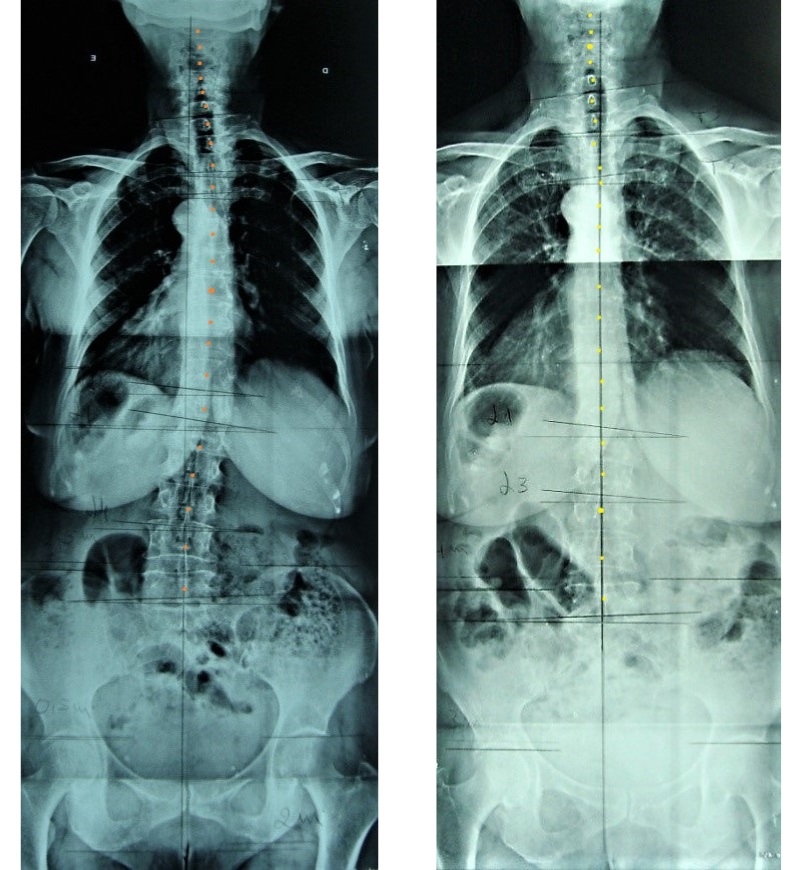

Quiropraxia

Abordagem terapêutica que procura corrigir desalinhamentos da coluna e articulações, promovendo o equilíbrio do sistema nervoso e a funcionalidade do corpo. Focada no bem-estar integral, ajuda a aliviar dores, melhorar a postura e restaurar a mobilidade através de ajustes precisos e técnicas manuais.

Ideal para quem procura tratar dores crónicas, tensões musculares e otimizar a saúde de forma natural. Uma rotina de ajustamentos quiropráticos periódicos ajuda-o a manter-se mais saudável e sem sintomas.